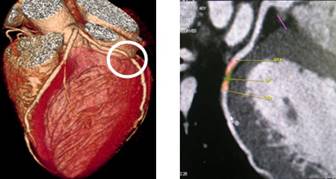

320排螺旋CT具备16cm宽覆盖探测器,实现动态容积扫描,360度的各向同性采集能力及[email protected]%密度分辨率的量子探测器,一次心跳全心脏采集,一圈扫描器官成像,一次检查完成多重任务,实现真正的动态容积体灌注及心脏、神经一站式检查;西门子Flash炫速CT扫描系统,具备两套同时旋转的X射线球管及探测器,实现了43cm/s的极快CT扫描速度和75 ms的时间分辨率,完成全胸扫描仅需0.6秒,使得患者做心脏扫描时无须食用β-受体阻滞药,亦无须屏气,并可实现低于1mSv的超低辐射剂量,配置第二代双能量、宽151级纯化能谱,组织鉴别能力进一步提高,可开展多达10余种双能量成像应用。

※肝脏、胰腺、肾脏CT-DSA 及灌注功能一站式检查